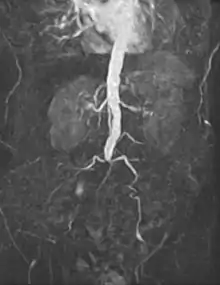

- Abdominal

An abdominal aortic aneurysm (AAA) refers to aneurysmal dilation of the aorta confined to the abdominal cavity. Most commonly, aneurysms are asymptomatic and located in the infrarenal position. Often, they are discovered incidentally or on screening exams in patients with risk factors such as a history of smoking. Patients with aneurysms which have a diameter less than 5 cm are at <1% rupture risk per year. When the aneurysm meets size criteria it can be treated with aortic replacement or EVAR.

Abdominal aortic aneurysms can be classified as infrarenal, juxtarenal, pararenal or suprarenal as depicted in the illustration.